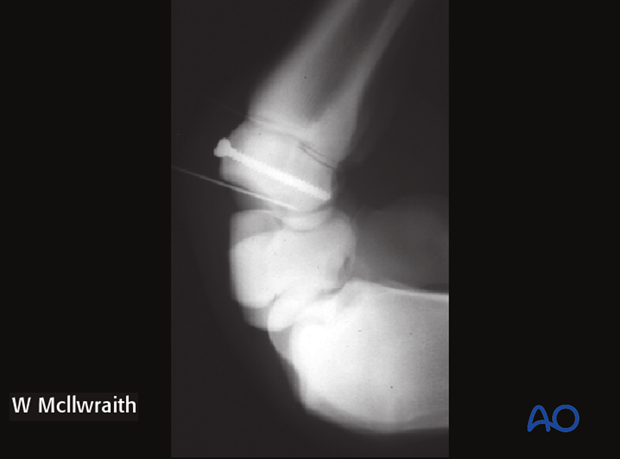

A flexed LM and ...

…skyline radiographinc views are taken to provide the proximal-distal location of the lag screw.

The drill depth can be verified using an intraoperative radiograph.

Intraoperative radiographs are take to confirm screw length and correct positioning.

Intraoperative radiographs are taken to confirm screw length and correct positioning.